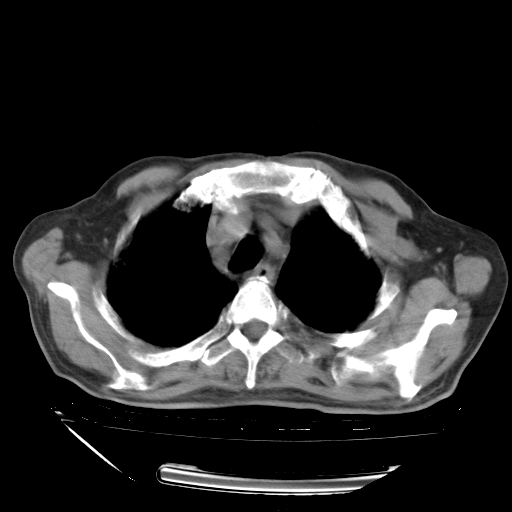

甲强龙80mg/日+抗结核治疗(异烟肼+利福霉素+乙胺丁醇)10天。复查肺部CT。

治疗10天肺部CT